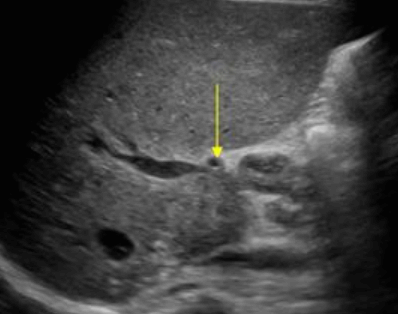

Choledocholithiasis US finding

- 총담관 내에 후방음향음영을 동반한 강한 에코가 관찰된다.

- 총담관의 확장 소견이 보인다. ( 7mm 이상)

- 담석이 관찰되지 않고 간외, 간내담관의 확장소견을 시사하는 엽총징후(shotgun sign)이나 평행관 징후(parallel channel sign)가 관찰되기도 한다.

- 엽총징후(shotgun sign): 간외 담관이 확장되어 간외 담관과 문맥이 이웃해 관찰된다.

- 평행관 징후(parallel channel sign): 간내 담관이 확장되어 인접하고 있는 문맥과 나란히 2개의 관상구조로 나타난다.